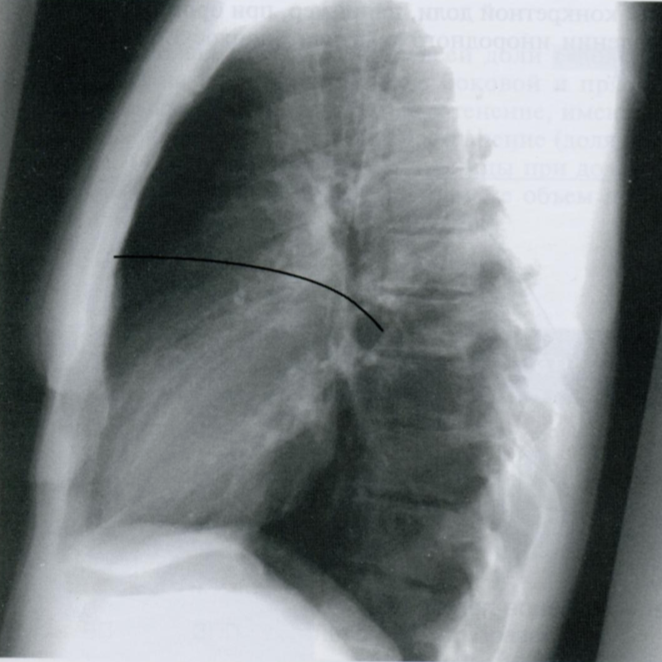

Q

Какая структура отмечена линией на снимке?

A

Горизонтальная междолевая щель легкого.